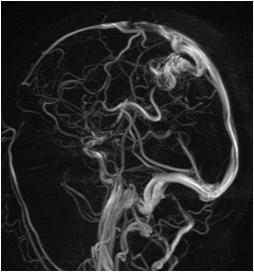

Fig 1 — CT Imaging from a patient of Basal Ganglia hemorrhage in the present study